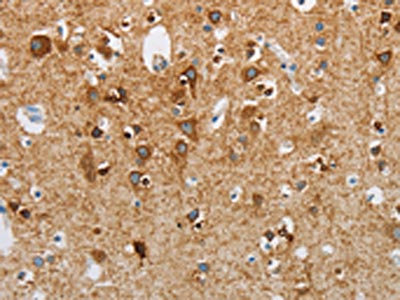

The image on the left is immunohistochemistry of paraffin-embedded Human brain tissue using CSB-PA260598(NEK5 Antibody) at dilution 1/25, on the right is treated with synthetic peptide. (Original magnification: ×200)